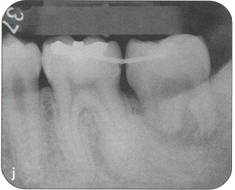

Fi 545e45f g 5-4f Extracted second molar, which will be discarded. Fi 545e45f g Extracted donor tooth. The amount of periodontalligament is adequate. Transplantation was performed 6 weeks after extraction of the tooth from the recipient site. Fi 545e45f g 5-4h View of the donor site and preparation of the recipient site. |

Fi 545e45f g 5-4i After the gingival flap has been sutured and the donor tooth has been splinted. The distal aspect of the donor tooth is closed as tightly as possible. Fi 545e45f g 5-4j After transplantation. Fi 545e45f g 5-4k Two weeks after trans plantation |

Fi 545e45f g 5-41 Six weeks after transplantation. The root canals have been cleaned, shaped, and filled with calcium hydroxide. Fi 545e45f g 5-4m Three months after transplantation. The radiograph was taken after removing the splint. Fi 545e45f g 5-4n Seven months after transplantation. |